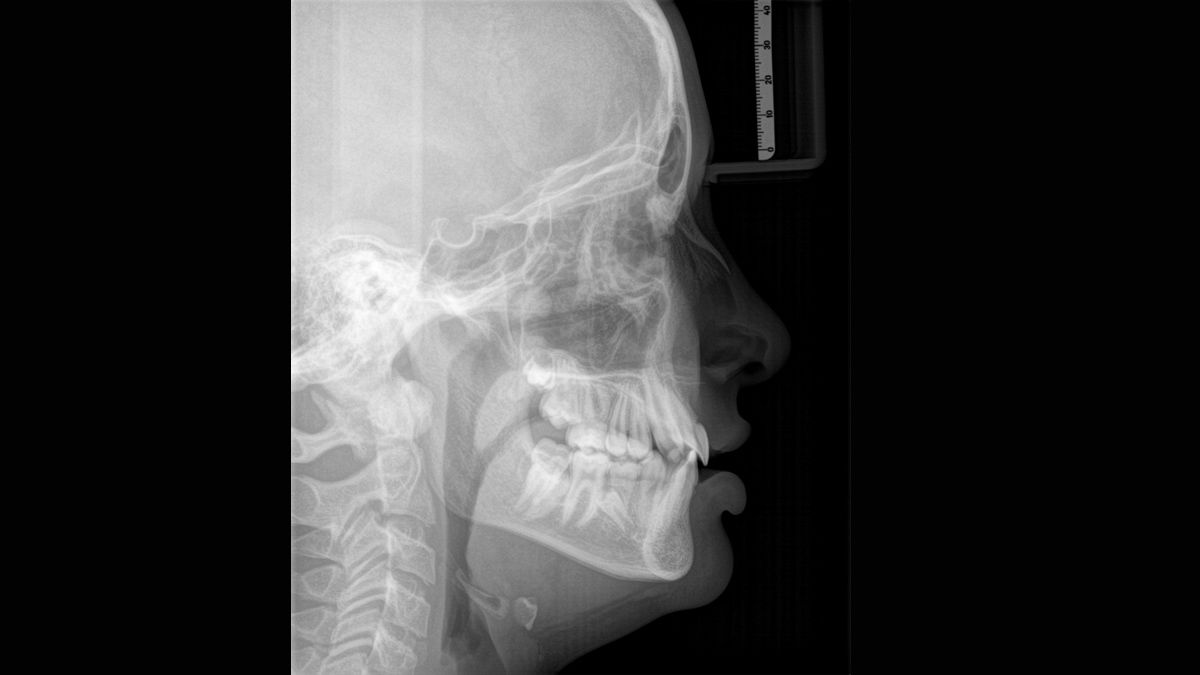

Tecnología Sharp Layer (SL)

La tecnología SL le permite generar multiples imágenes durante una única rotación. Los fragmentos con mejor enfoque se combinan automáticamente para formar una imagen de rayos X con nitidez incomparable (ideal para observar piezas multiradiculares).

Algoritmo de software ASTRA

ASTRA mejora considerablemente la calidad de las imágenes panorámicas 2D y cefalométricas. Este algoritmo de reconstrucción estructurado anatómicamente genera una imagen con mayores contrastes sin la aparición de bordes indefinidos.